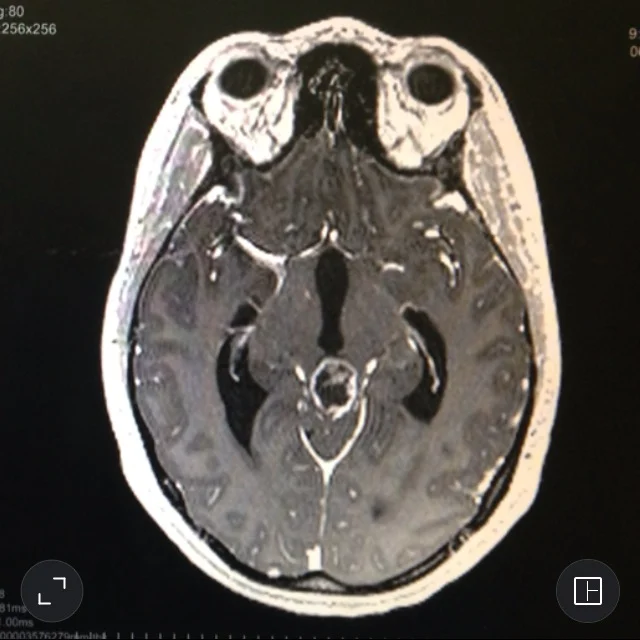

At age twenty-four Hebron was diagnosed with an inoperable brain tumor and she experienced a sea change as an artist and person becoming passionate about the patient experience. As a cancer survivor and patient advocate, she has performed at personal as well as public art events and been the featured artist for UCLA’s Heart of the Brain gala as well as a contributing artist for their Spirit of Judi gala. She had exhibitions at the Hoyt Gallery at the USC Keck School of Medicine as part of the H.E.A.L. program’s mission to foster enhanced understanding between patients and future health care professionals, and at the Jennifer Diamond Cancer Resource Library at the USC Norris Comprehensive Cancer Center as part of their Survivor Art Series.